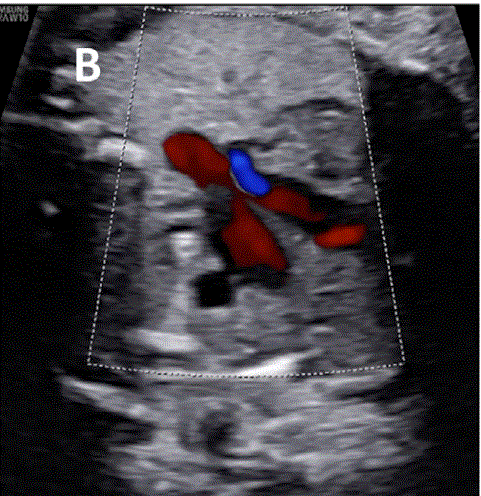

图27进展性主动脉狭窄。一例23周胎儿的严重主动脉狭窄,伴有扩张和低动力性左心室(LV)伴心内膜弹性纤维变性。(A) 彩色多普勒显示,主动脉瓣(箭头)开始出现花彩血流(左),频谱多普勒显示阶差为 25 毫米汞柱(右(B) 二尖瓣(MV)流入是单相的,持续时间短(左),二尖瓣反流提示左心室收缩压高(46毫米汞柱压力梯度加左心房压力;右图)。(C)存在逆行主动脉弓流(红色,左)和左至右心房流(红色、右)是预测由于通过左心的流量减少而在妊娠期间发展的进行性左心发育不全的额外发现。(D)LV逐渐变为球状,长度缩短,到36周时不再形成心尖。

图29胎儿Ebstein异常和TV发育不良。(A)在该胎儿中,严重的三尖瓣反流与进行性心脏增大有关,尤其是右心房(RA)扩张,如这些在19周和34周时的系列图像所示,并且可能与心力衰竭/水肿的演变有关。(B-D)四腔切面中胎儿严重Ebstein异常显示严重心脏扩大的图像。(C)从矢状切面可见广泛的三尖瓣反流(箭头),由于室间隔瓣叶移位,反流起源于TV瓣环下方,甚至向 RV 流出道射流。彩色多普勒和 CW 多普勒显示也有连续的肺动脉反流。(D) 后一项发现表明,右心室无法产生足够的压力来打开肺动脉瓣